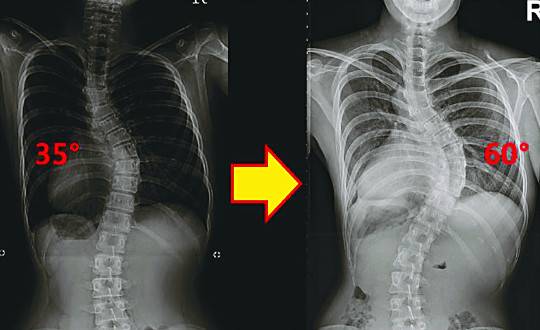

올해 중3인 딸을 둔 안수진(46·인천 남동구)씨는 우연히 딸의 허리가 휜 사실을 발견했다. 초등 6학년 초 어느 날, 딸의 등 오른쪽 날개뼈 있는 부분이 툭 튀어나와 있고 오른쪽 어깨가 왼쪽 보다 높게 보였다는 것. 놀라서 인근 대학병원에서 X선 촬영을 했더니 척추가 35도나 옆으로 휘어져 있었다. 안씨는 “육안으로 보일 정도로 많이 진행됐는데, 아이가 아프다거나 불편하다고 한 적이 없어 의식하지 못했다. 무심했던 것 같다”고 했다.

딸은 매일 척추 보조기를 끼고 등교했고 수영 등 운동도 게을리 하지 않았지만 1년 만에 휘어진 각도가 60도로 커져 결국 수술을 받았다. 앞 가슴이 왼쪽으로 틀어져 올라가고 반대편은 처져 옷 입기조차 불편해 진 것. 무엇보다 휜 각도가 더 커지면 폐와 위 같은 장기가 틀어진 뼈에 눌려 숨쉬기 곤란하고 소화장애도 올 수 있다는 걱정이 컸다.

청소년기 척추측만증을 발견하고도 방치해 치료 시기를 놓치는 경우도 많다. 유모(25·여)씨는 중1 때 35도의 척추측만증 진단을 받았지만 더 이상 병원을 찾지 않았고 최근 검사결과 60도까지 휘어진 것으로 확인됐다. 서 교수는 “나이 많은 성인의 경우 척추가 굳어서 수술로도 교정이 잘 안되므로 가능하면 일찍하는 것이 좋다”고 말했다.